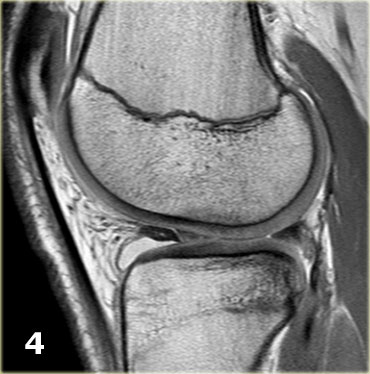

Như bạn đã đoán được qua tiêu đề của đoạn này, đây là một trường hợp sụn chêm lật (flipped meniscus).

Sụn chêm lật là một dạng đặc biệt của rách dạng quai xô (bucket-handle tear).

Sụn chêm lật xảy ra khi mảnh vỡ của sừng sau bị lật ra phía trước, khiến sừng trước của sụn chêm có vẻ to hơn bình thường.

- Sừng sau quá nhỏ và sừng trước có vẻ to hơn với đường viền không đều.

- Thoạt nhìn có vẻ như có một đường rách dọc ở sừng trước, nhưng thực chất phần sau của cấu trúc này chính là phần lật của sừng sau bị rách.

Cấu trúc phía trước là sừng trước.

Cũng cần lưu ý tình trạng phù tủy xương khu trú và dấu ấn lõm sụn khớp. - Cấu trúc phía trước là sừng trước.

- Một số bất thường ở phần sau.

- Phần sau di chuyển về phía đuôi (caudal).

- Trong hố gian lồi cầu là điểm nối giữa mảnh di lệch và phần còn lại của sừng sau.